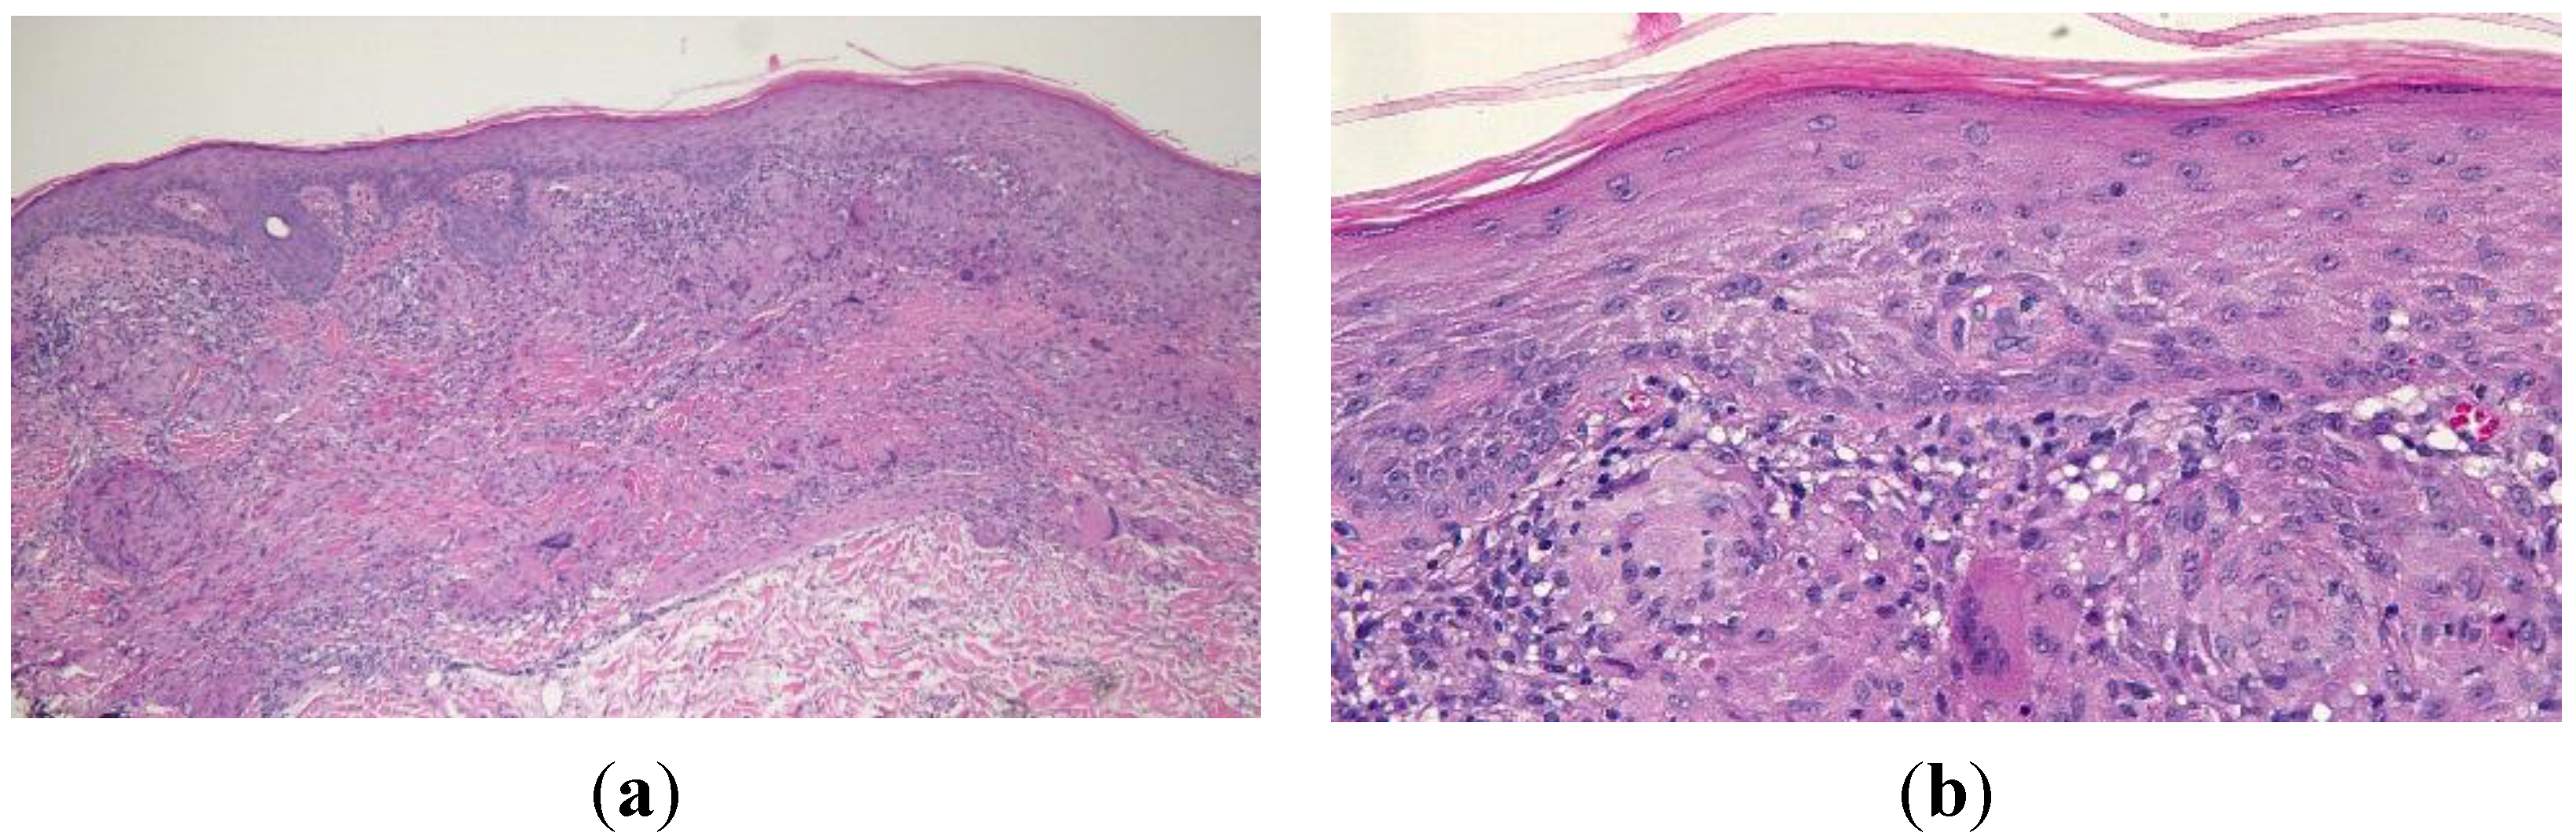

Histologic examination of the skin from his left calf revealed sarcoidal granulomas comprised of epithelioid-appearing histiocytes within the superficial dermis. Langerhans cells were present. The overlying epidermis demonstrated areas of hyperplasia and hyperkeratosis. A lichenoid lymphocytic infiltrate was also observed at the dermal-epidermal junction. Spindle-shaped interstitial histiocytes could be seen in the upper portions of the dermis. The spindle-shaped cells as well as the epithelioid component stained positively for CD68 and negatively for cytokeratin AE1/3 (Figure 5). Correlation of the clinical presentation of the lesion and the pathology was consistent with cutaneous sarcoidosis. The patient applied betamethasone dipropionate 0.05% cream twice a day for two weeks and the lesion resolved.

Figure 5. Low (a) and high (b) magnification views of the sarcoidal granuloma taken from the left calf of a 54-year-old man. Low magnification view (a) shows hyperplasia and hyperkeratosis in the overlying epidermis as well as a lichenoid lymphocytic infiltrate at the dermal-epidermal junction. Langerhans cells and spindle-shaped interstitial histiocytes can be observed in the high magnification view (b). [Hematoxylin and eosin; a = ×10, b = ×40].